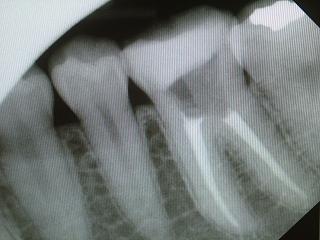

わからない時はデンタルX線で確認です。

レントゲンにて確認。

根管治療(歯内療法)の症例